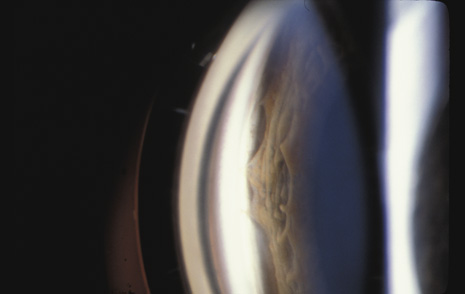

Vitreous Traction Tears Weidenthal and Schepens76 concluded, from their study of trauma to enucleated pig eyes, that rapid equatorial expansion is responsible for tears at the anterior and posterior borders of the vitreous base. Because the vitreous body is relatively elastic, slow compression of the eye is not deleterious. However, when the eye is rapidly compressed, the vitreous does not have enough time to stretch. As a consequence, there is strong traction at the vitreous base that may cause tears at its anterior and posterior borders. Scott suggested an alternative mechanism for these tears (J. Scott, personal communication, 1982). He suggested that retrodisplacement of the cornea and aqueous drives the lens-iris diaphragm backward against the anterior vitreous, forcing the vitreous back and pushing the vitreous base away from its adherence to the pars plana epithelium and anterior retina. Whatever the mechanism, a portion of the vitreous base can be avulsed from the retina and pars plana. The avulsed base looks like a ribbon floating in the vitreous cavity. Closer inspection reveals that the vitreous base remains in contact with the adjacent vitreous cortex, which is also avulsed (Fig. 15). Avulsion of the vitreous base is pathognomonic of blunt trauma and may have considerable medicolegal importance. Unfortunately, in most cases of severe trauma, the vitreous base does not separate cleanly from the retina and pars plana epithelium. It remains adherent, tearing these tissues. The retina can be torn along the posterior margin of the vitreous base, or the nonpigmented pars plana epithelium can be torn along the anterior margin of the vitreous base, or both can be torn simultaneously. Similarly, if the vitreous is strongly adherent to either lattice degeneration or a vitreoretinal scar posterior to the vitreous base, a posterior flap tear may occur.77 Any of these tears can cause a retinal detachment.